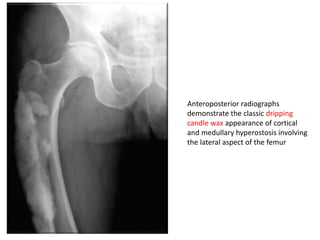

Anteroposterior radiographs

demonstrate the classic dripping

candle wax appearance of cortical

and medullary hyperostosis involving

the lateral aspect of the femur